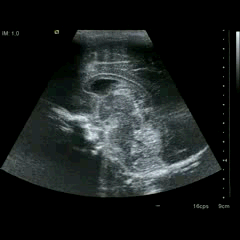

En la imagen 3 ves una imagen de un lipoma, mide 7 cms, la huella de la sonda mide 5cms, la «panoramic view» posee una regla centimetrada que sigue el contorno de la imagen, justo en la profundidad de la misma y lo marca la flecha amarilla. La profundidad la marca la flecha roja y la flecha blanca marca el rango centimetral de los 5cms, fíjate que la línea blanca es ligeramente mayor cada 5 cms. Sirve de referencia, como en la imagen 4 donde ves una colección en el glúteo de más de 10 cms.